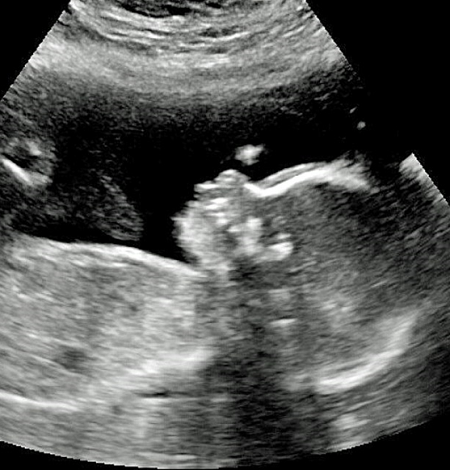

Ngay từ khi còn trong bụng mẹ, các bác sĩ đã siêu âm thấy rõ mái tóc dài của cậu bé, mái tóc khi ấy dài chừng 5 inch (12,7cm).

Cậu được phát hiện có nhiều tóc từ khi trong bụng mẹ. |

Angie nói: "Lần đầu tiên chúng tôi nhận ra đứa trẻ có nhiều tóc là khi siêu âm, khi bác sĩ của tôi nói" wow, đứa bé có rất nhiều tóc. "